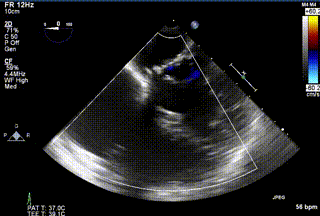

2021年12月24日,復(fù)旦大學(xué)附屬中山醫(yī)院葛均波院士團(tuán)隊成功應(yīng)用LuX-Valve Plus為一例極重度三尖瓣反流(TR)合并房顫、房缺的患者完成了經(jīng)血管三尖瓣置換術(shù),這是在前基礎(chǔ)上,本周完成的第三例經(jīng)血管三尖瓣置換手術(shù),葛均波院士、周達(dá)新教授等與心外科魏來教授、賴顥教授,心超室的潘翠珍教授、李偉教授及麻醉科的郭克芳教授共同完成了本周手術(shù),均獲得圓滿成功!患者術(shù)后超聲顯示無TR,臨床癥狀明顯改善。本周手術(shù)的成功也為LuX-Valve Plus救治性臨床研究添上了濃墨重彩的一筆。

三例患者入院后,葛均波院士團(tuán)隊周達(dá)新教授、潘文志教授、張源博士、陳莎莎博士及心超室的潘翠珍教授、李偉教授對患者的情況進(jìn)行詳細(xì)評估和討論,最終決定為三例患者選擇LuX-Valve Plus40mm、50mm和50mm型號的瓣膜進(jìn)行手術(shù)治療。手術(shù)后即刻拔除氣管插管,術(shù)后患者三尖瓣反流癥狀得到顯著改善,復(fù)查心超結(jié)果顯示人工三尖瓣瓣膜支架固定穩(wěn)定,瓣葉關(guān)閉形態(tài)未見異常,未見明顯反流。